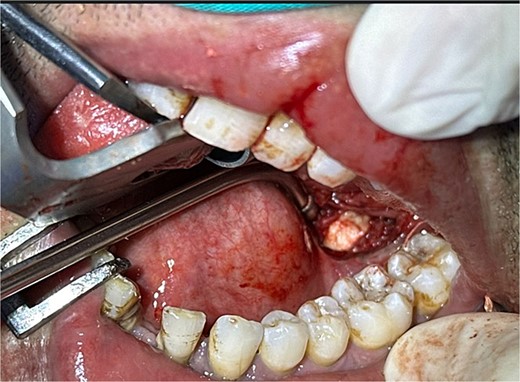

The accuracy of navigation was periodically verified by referencing stable bony landmarks, such as the mental foramen and mandibular condyles, with the navigation probe. Realignment was conducted as needed to ensure consistent anatomical mapping and precise localization of the submandibular stone (Fig. 2). After surface registration, a 1 cm mucosal incision was made intraorally at the nearest point indicated by the navigation pointer, parallel to the anticipated course of the Wharton duct. Blunt dissection was performed to expose the duct, with navigation toward the stone guided by the system. Great care was taken to protect the lingual nerve throughout the procedure. The depth of dissection was gradually advanced by periodically verifying the position with the navigation pointer probe (Fiagon) to maintain precision. During dissection, the stone was accurately located within the gland parenchyma using real-time visualization, and it became palpable, distinguished by its unique color and texture (Fig. 3). The stone was fragmented and removed in pieces because it was fixed (Fig. 4). The surgical field was flushed with saline to remove any residual stone debris, and the incision was closed with 4/0 Vicryl, which is an absorbable suture.

Intraoperative navigation identifying the location of the sialolith.

Intraoral extraction of the submandibular gland stone during the procedure.